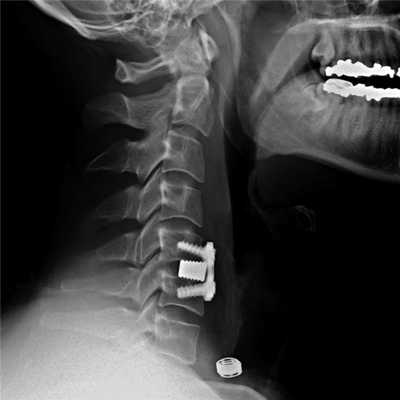

На шейных уровнях применяются и стабилизирующие тактики оперативных вмешательств, каждая из которых, кстати, может идти совместно и с другими видами операций. Наиболее популярные из стабилизирующих методов:

- - неподвижное соединение (сращивание) двух или более позвонков при их нестабильности;

Импланты шейного отдела позвоночника на рентгене.

Если клиника симптомов не поддается консервативной терапии или неинвазивные способы не могут быть задействованными ввиду сильно прогрессирующего стеноза, назначается операция. Вмешательство предполагает использование декомпрессионной ламинэктомии под общим наркозом. При комбинированной проблеме, например, вместе с грыжей, ее сочетают с микродискэктомией и спондилодезом. При спондилодезе осуществляют скрепление смежных позвонков металлическими фиксаторами (стержнями, пластинами, крючками и пр.), установку межтеловых имплантатов или вживление костного трансплантата с металлической гильзой.

Установка металлической конструкции.